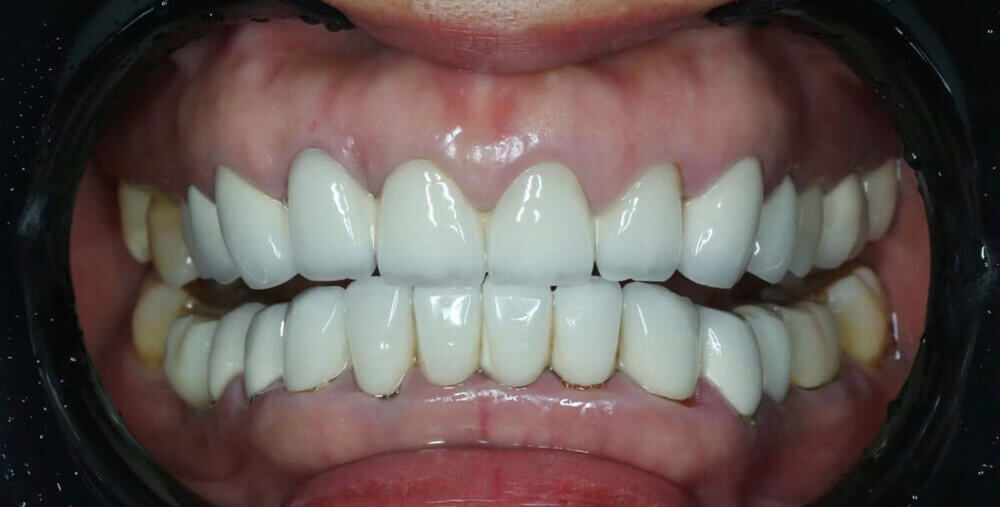

A photo of our PFM bridge, taken by one of our dentist customers from the US. Such professional photo enables us to study teeth clearly.

We may also need high-resolution photos that can show different angles of ALL your teeth. Usually orthodontists and dentists send us photos that allow us to thoroughly study patients’ oral conditions, while patients’ photos cannot.